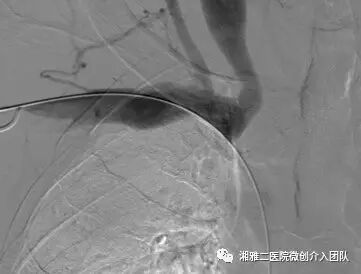

穿刺成功后行顺行性造影,了解狭窄的部位和程度

造影所见,可见无名静脉闭塞并侧枝形成

以上为再通过程